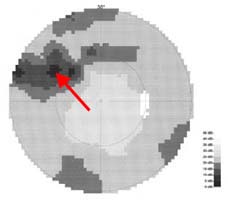

Modrá šipka - ukazuje plochu na sítnici, která obsahuje nervová vlákna. Sítnice je jemně proužkovaná, světlejší, cévy "jsou jako pod závojem". Červená šipka - ukazuje místo bez nervových vláken. Sítnice je tmavší, bez proužkování. Cévy jsou ohraničeny neobvykle ostře.